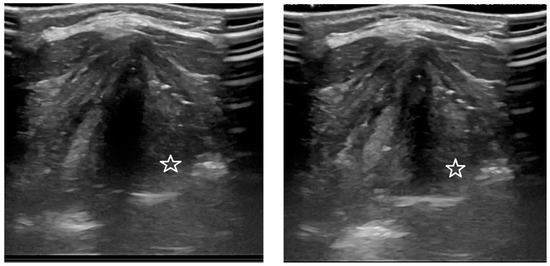

3.1. Analysis of the Qualitative Data Obtained during Ultrasound and MRI in Patients with Goiter Compared to Direct Laryngoscopy

3.2. Analysis of the Quantitative Data Obtained Using Ultrasound and MRI Methods (GRE and TRUFI Sequences) before and after Thyroidectomy